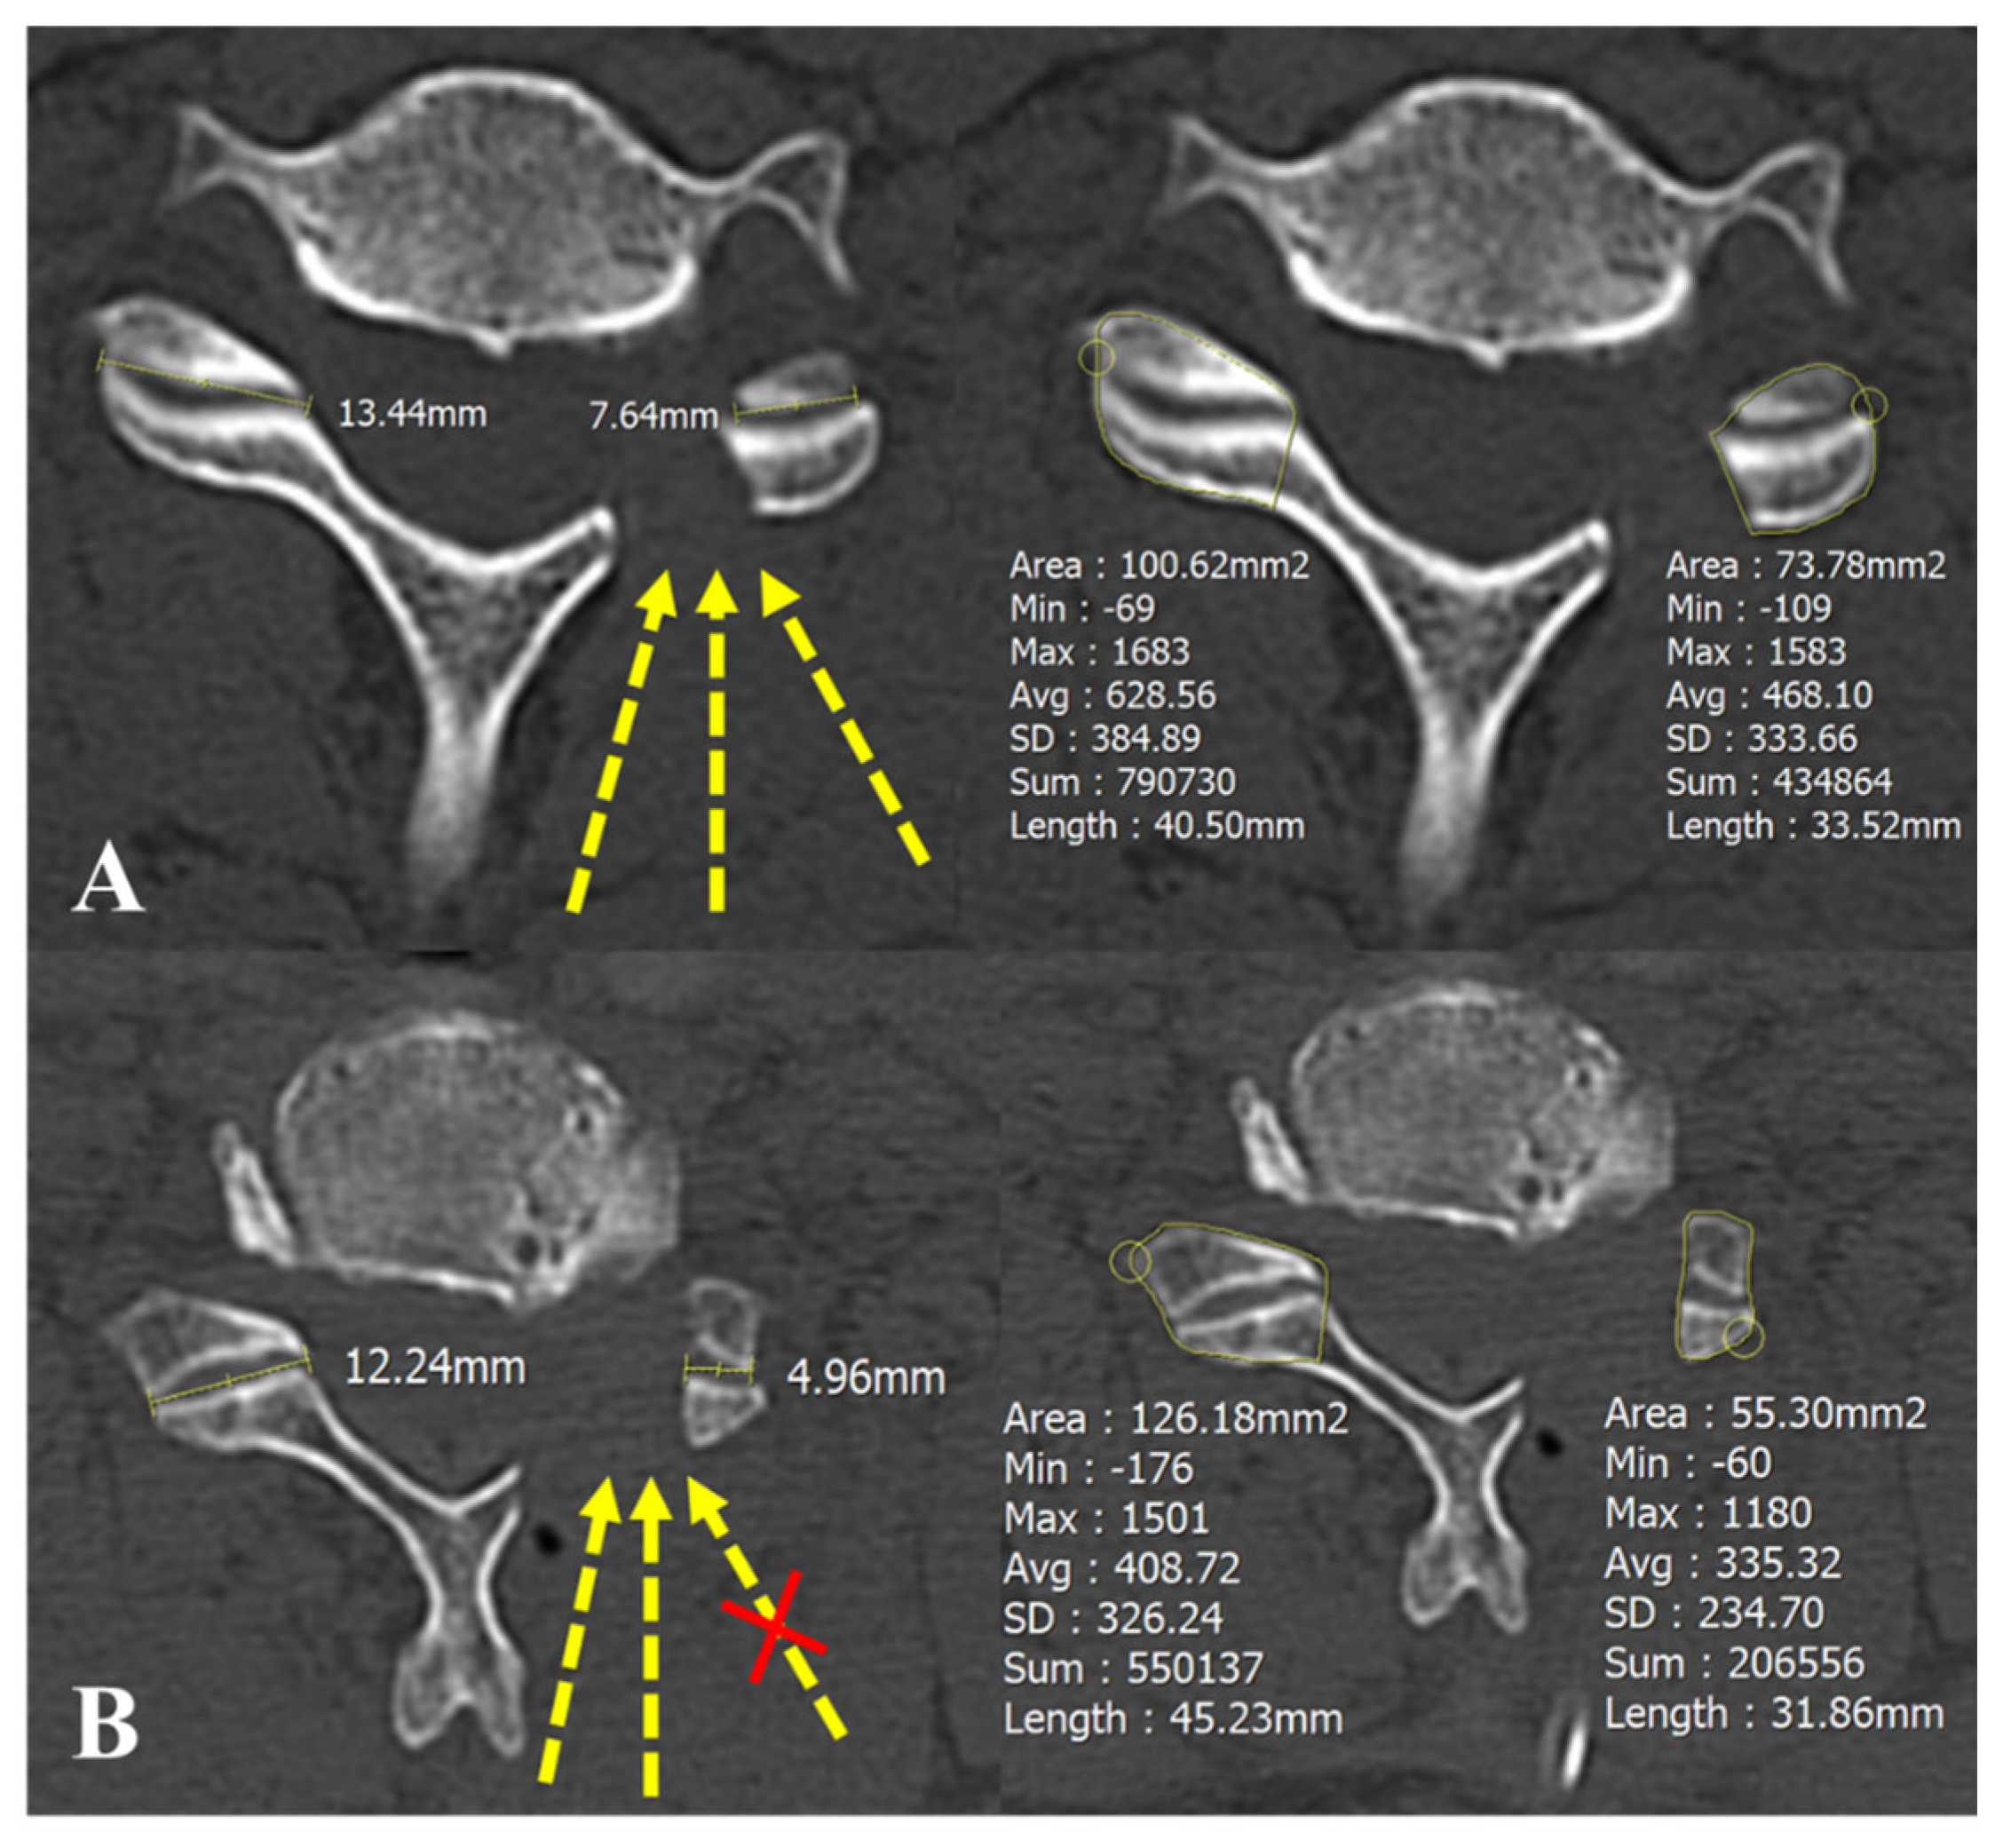

| Foraminal dimension (mm2) | 34.3 ± 8.5 | 31.5 ± 7.8 | 0.16 |

| Post foraminal dimension (mm2) | 54.5 ± 8.2 | 53.3 ± 7.4 | 0.51 |

| Foraminal enlargement (%) | 63.8 ± 26.1 | 75.5 ± 34.6 | 0.13 |

| Bone bridge formation (n, %) | 6 (20%) | 16 (53.3%) | 0.01 * |

| Facetectomy width (%) | 43.2 ± 7.3 | 51.6 ± 11.3 | 0.01 * |

| Facetectomy area (%) | 40.5 ± 8.1 | 48.1 ± 10.4 | <0.01 * |